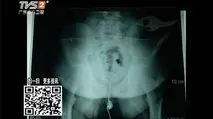

从医学上来说,如果男孩的睾丸发育超过4毫升的话,那么就已经属于性

六 青春发育的正常年龄范围女孩男孩乳房:8-13岁睾丸:9-14岁阴毛:11.